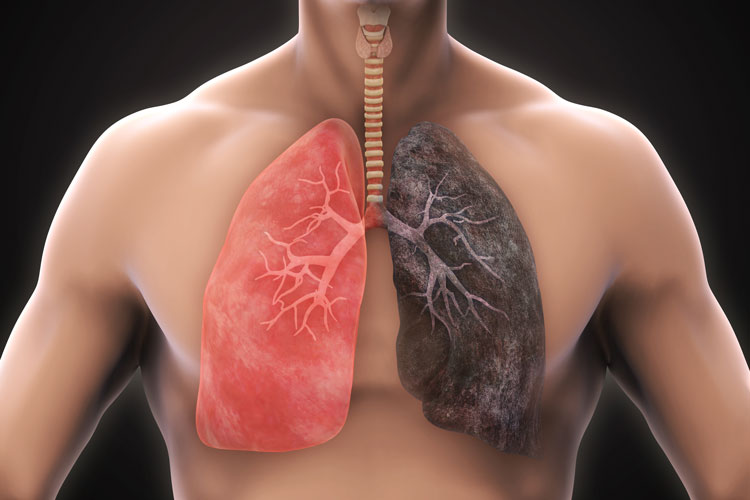

ফুসফুসের ক্যানসার প্রতিরোধ করতে ধূমপান ছেড়ে মাস্ককে সঙ্গী করুন

ধূমপান না করলেও হতে পারে ফুসফুসের ক্যানসার, রোগ দূরে রাখতে এ সব মানতেই হবে

ধূমপায়ী না হলেও হতে পারে ফুসফুসে ক্যানসার

ধূমপান ছাড়া এ সব কারণেও ফুসফুসে দানা বাঁধতে পারে ক্যানসার!